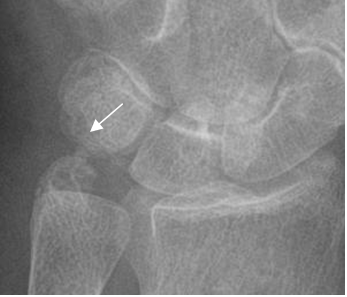

Fig 86. Impactación ulnar.

Rx AP. Apófisis estiloides de la ulna muy prominente, en contacto con el piramidal, sin cambios óseos asociados.